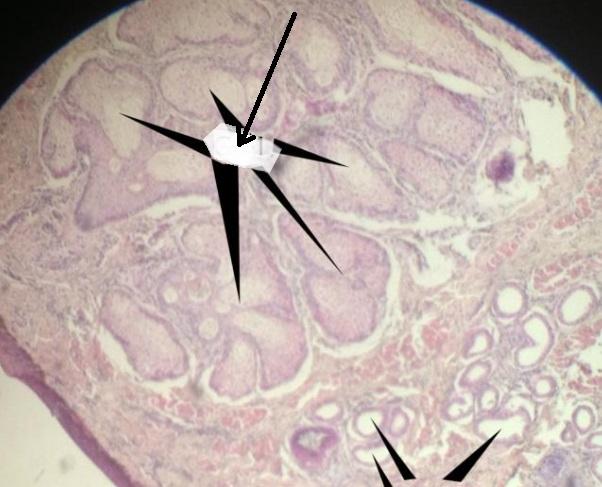

Pytanie 234

część guzowa przysadki gruczołowej (przysadka mózgowa zwierzęca)

Pytanie 235

naczynia zatokowe (przysadka mózgowa zwierzęca)